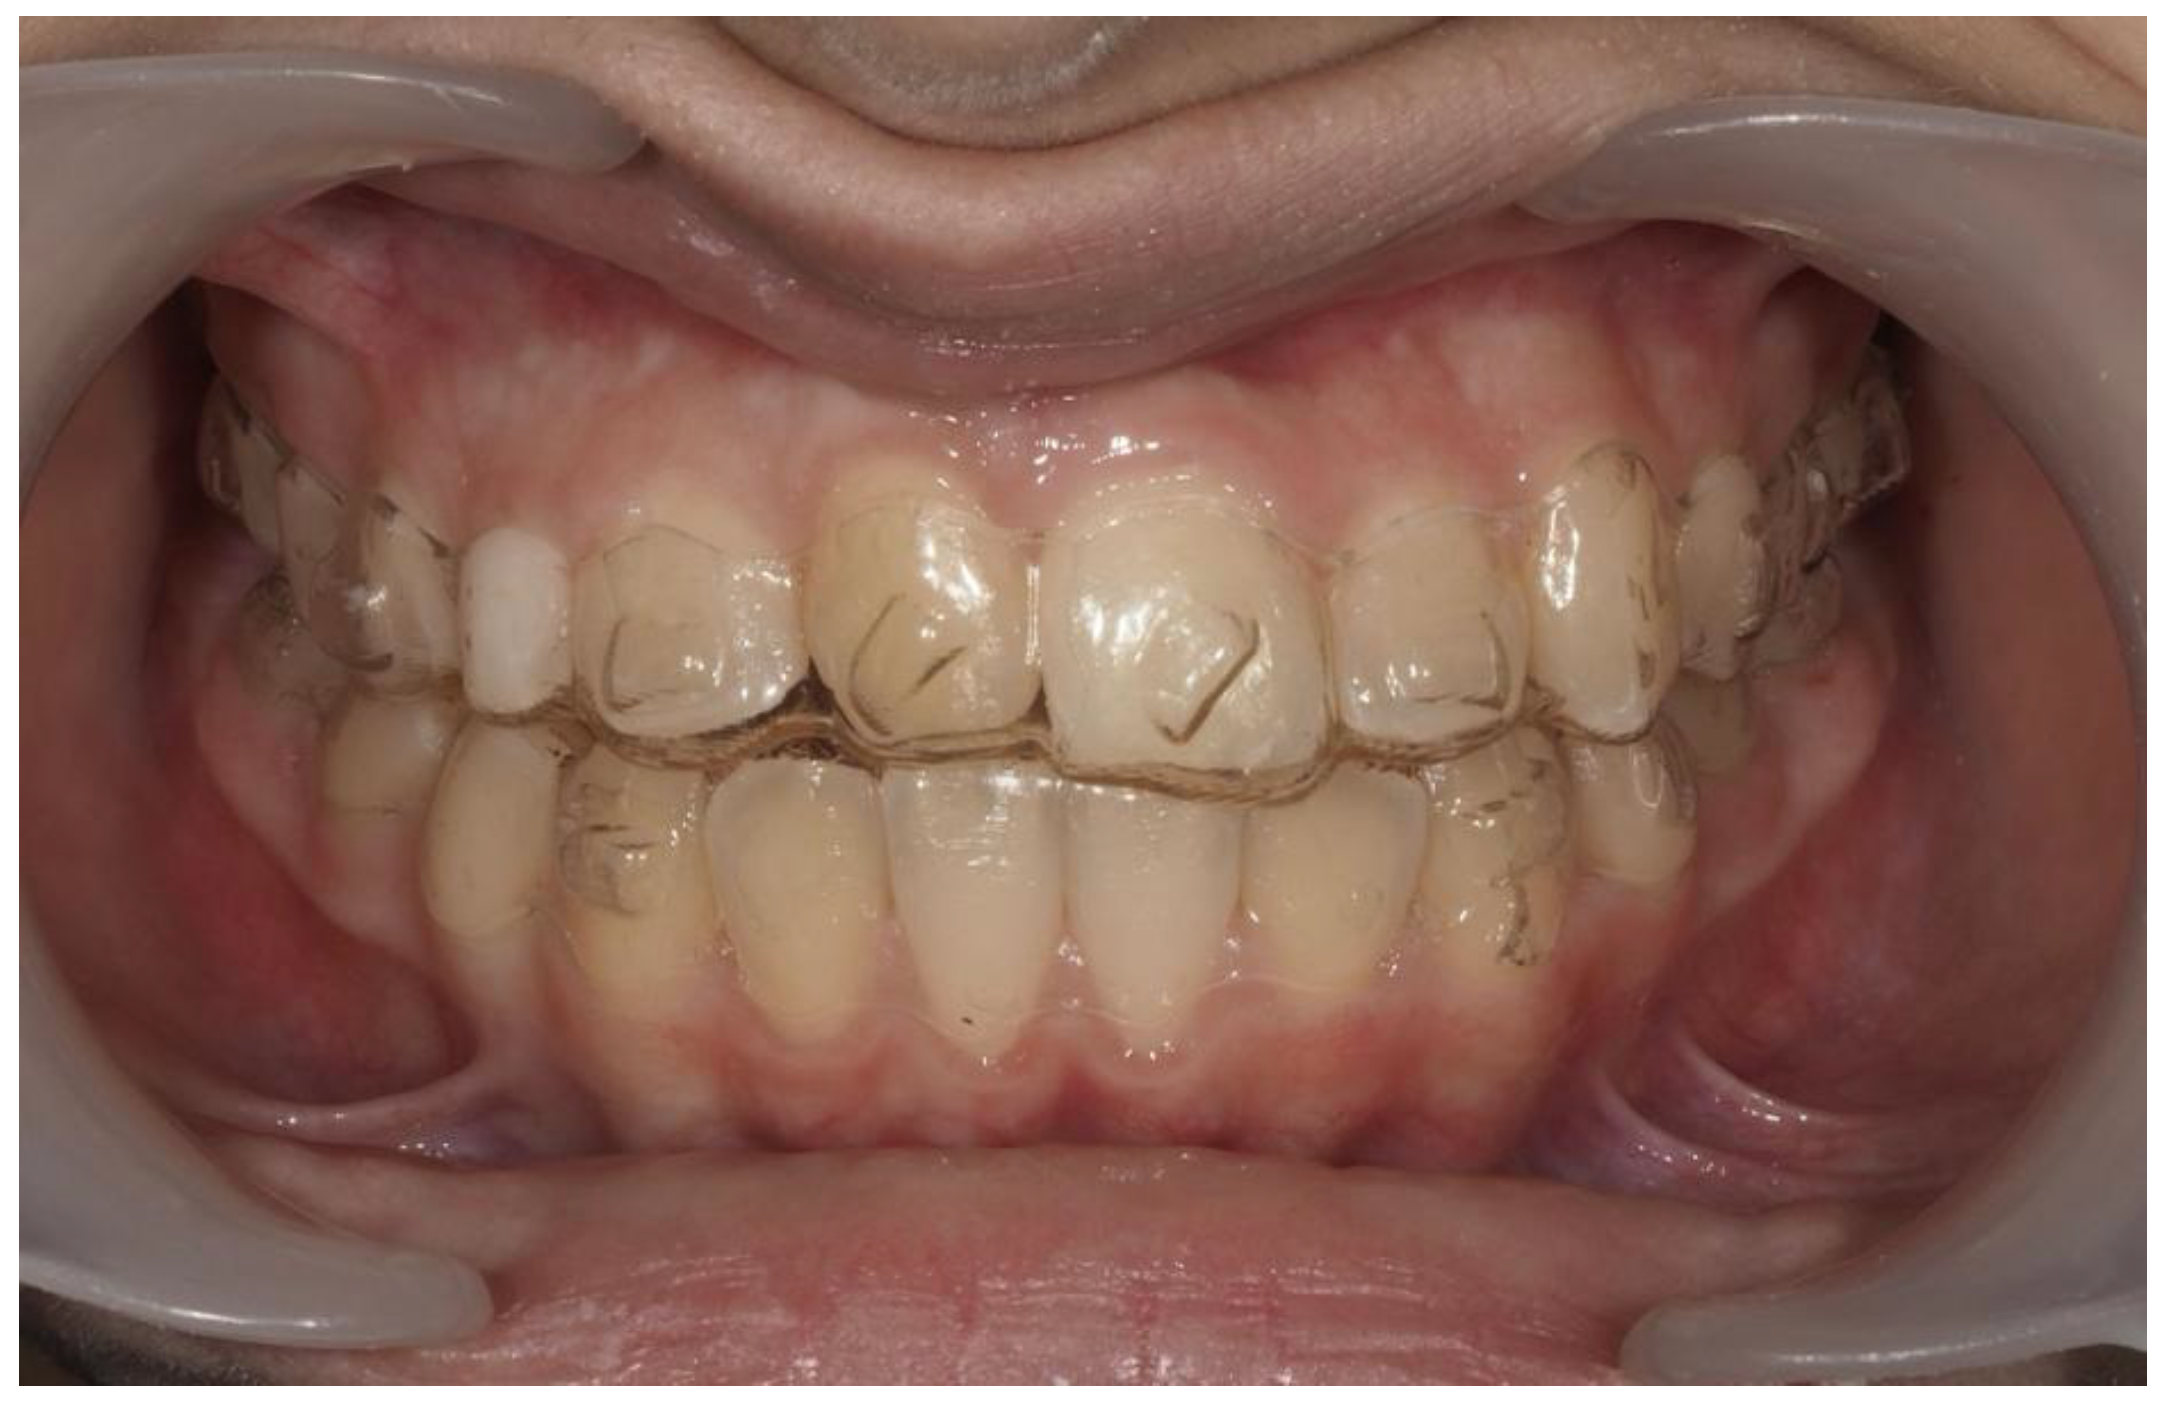

| Pinho T., Amaral R. 2025 | ♀ 13 YO | Mx.C.I1 | C | R | V (impacted) | Cl I | Maintained | -Total root resorption of tooth #11 due to the position of the ectopic canine |

3.2. Clinical Case